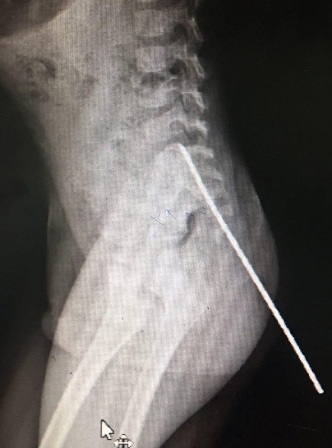

به گزارش دانشگاه علوم پزشکی قزوین که سه شنبه به ایرنا نمابر شده است، دکتر مهران مرادی متخصص جراحی مغز و اعصاب این مرکز درباره این بیمار خردسال گفت: میله از ناحیه کنار معقد وارد و تا نخاع کمری کودک پیش رفته بود که در یک جراحی 2 ساعته با بیشترین دقت و حساسیت، میله بدون هیچ عارضه ای از بدن بیمار خارج شد.

وی همچنین اظهار کرد: بیمار پس از عمل جراحی در بخش مراقبت های ویژه بستری و پس از بهبودی کامل، مرخص خواهد شد.